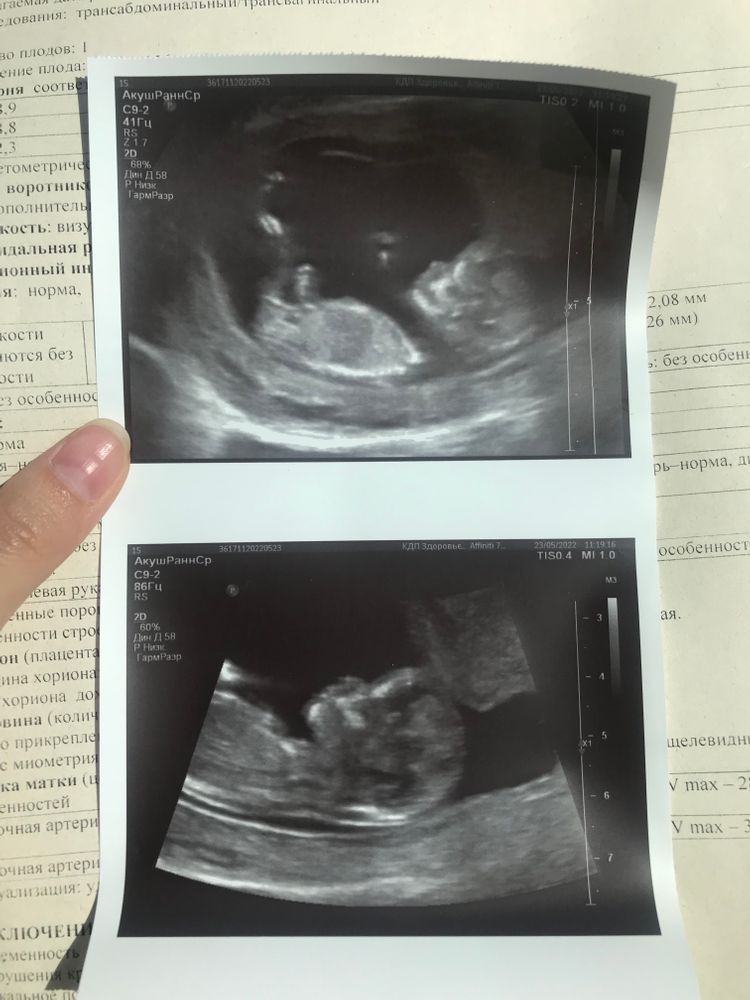

1 скрининг 12.2 нед

У меня похожий бугорок был у мальчика на первом УЗИ.

Чтобы предположить пол, нужно поймать на экране половой бугорок. Если он по углом, то мальчик, а если параллельно позвоночнику больше, то девочка. Ещё читала, что по форме головы, но неточно: круглый лоб - девочка, более квадратный лоб - мальчик. Но это то, что я читала))

Из-за ножки не видно)

Игритт, на таком сроке как раз боком и смотрят, тк половой бугорок одинаковый, только наклон разный. Там еще нет половых органов.  автор, у вас ножкой закрыто, бугорка не видно. По лбу определять - ерунда полнейшая. 🙂

Tina, так в том и дело, что закрыто))))